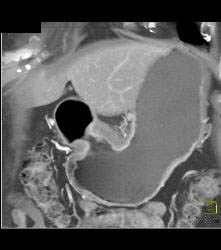

Antral Carcinoma